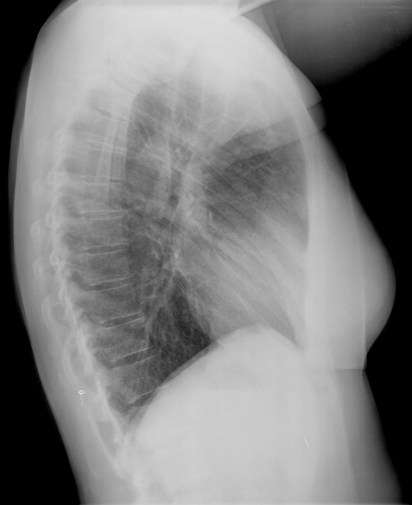

CASO: Febrícula y tos de 4 días de evolución.

Hallazgos:

- En la placa PA se observa una asimetría en los hilios pulmonares, el hilio izquierdo tiene una densidad aumentada.

- Tras examinar la placa lateral se observa un aumento de densidad en la columna que puede ser compatible con una condensación, es el signo de la desnificación vertebral.

SIGNO DE LA DENSIFICACIÓN VERTEBRAL: En la radiografía lateral normal, la densidad de la columna torácica tiende a disminuir desde la parte superior hasta el diafragma; la alteración de ese patrón por la presencia de una densidad superpuesta a la columna, indica la existencia de una consolidación pulmonar. Este signo adquiere especial valor cuando en la proyección posteroanterior la consolidación está oculta en el espacio retrocardíaco o en la base pulmonar.